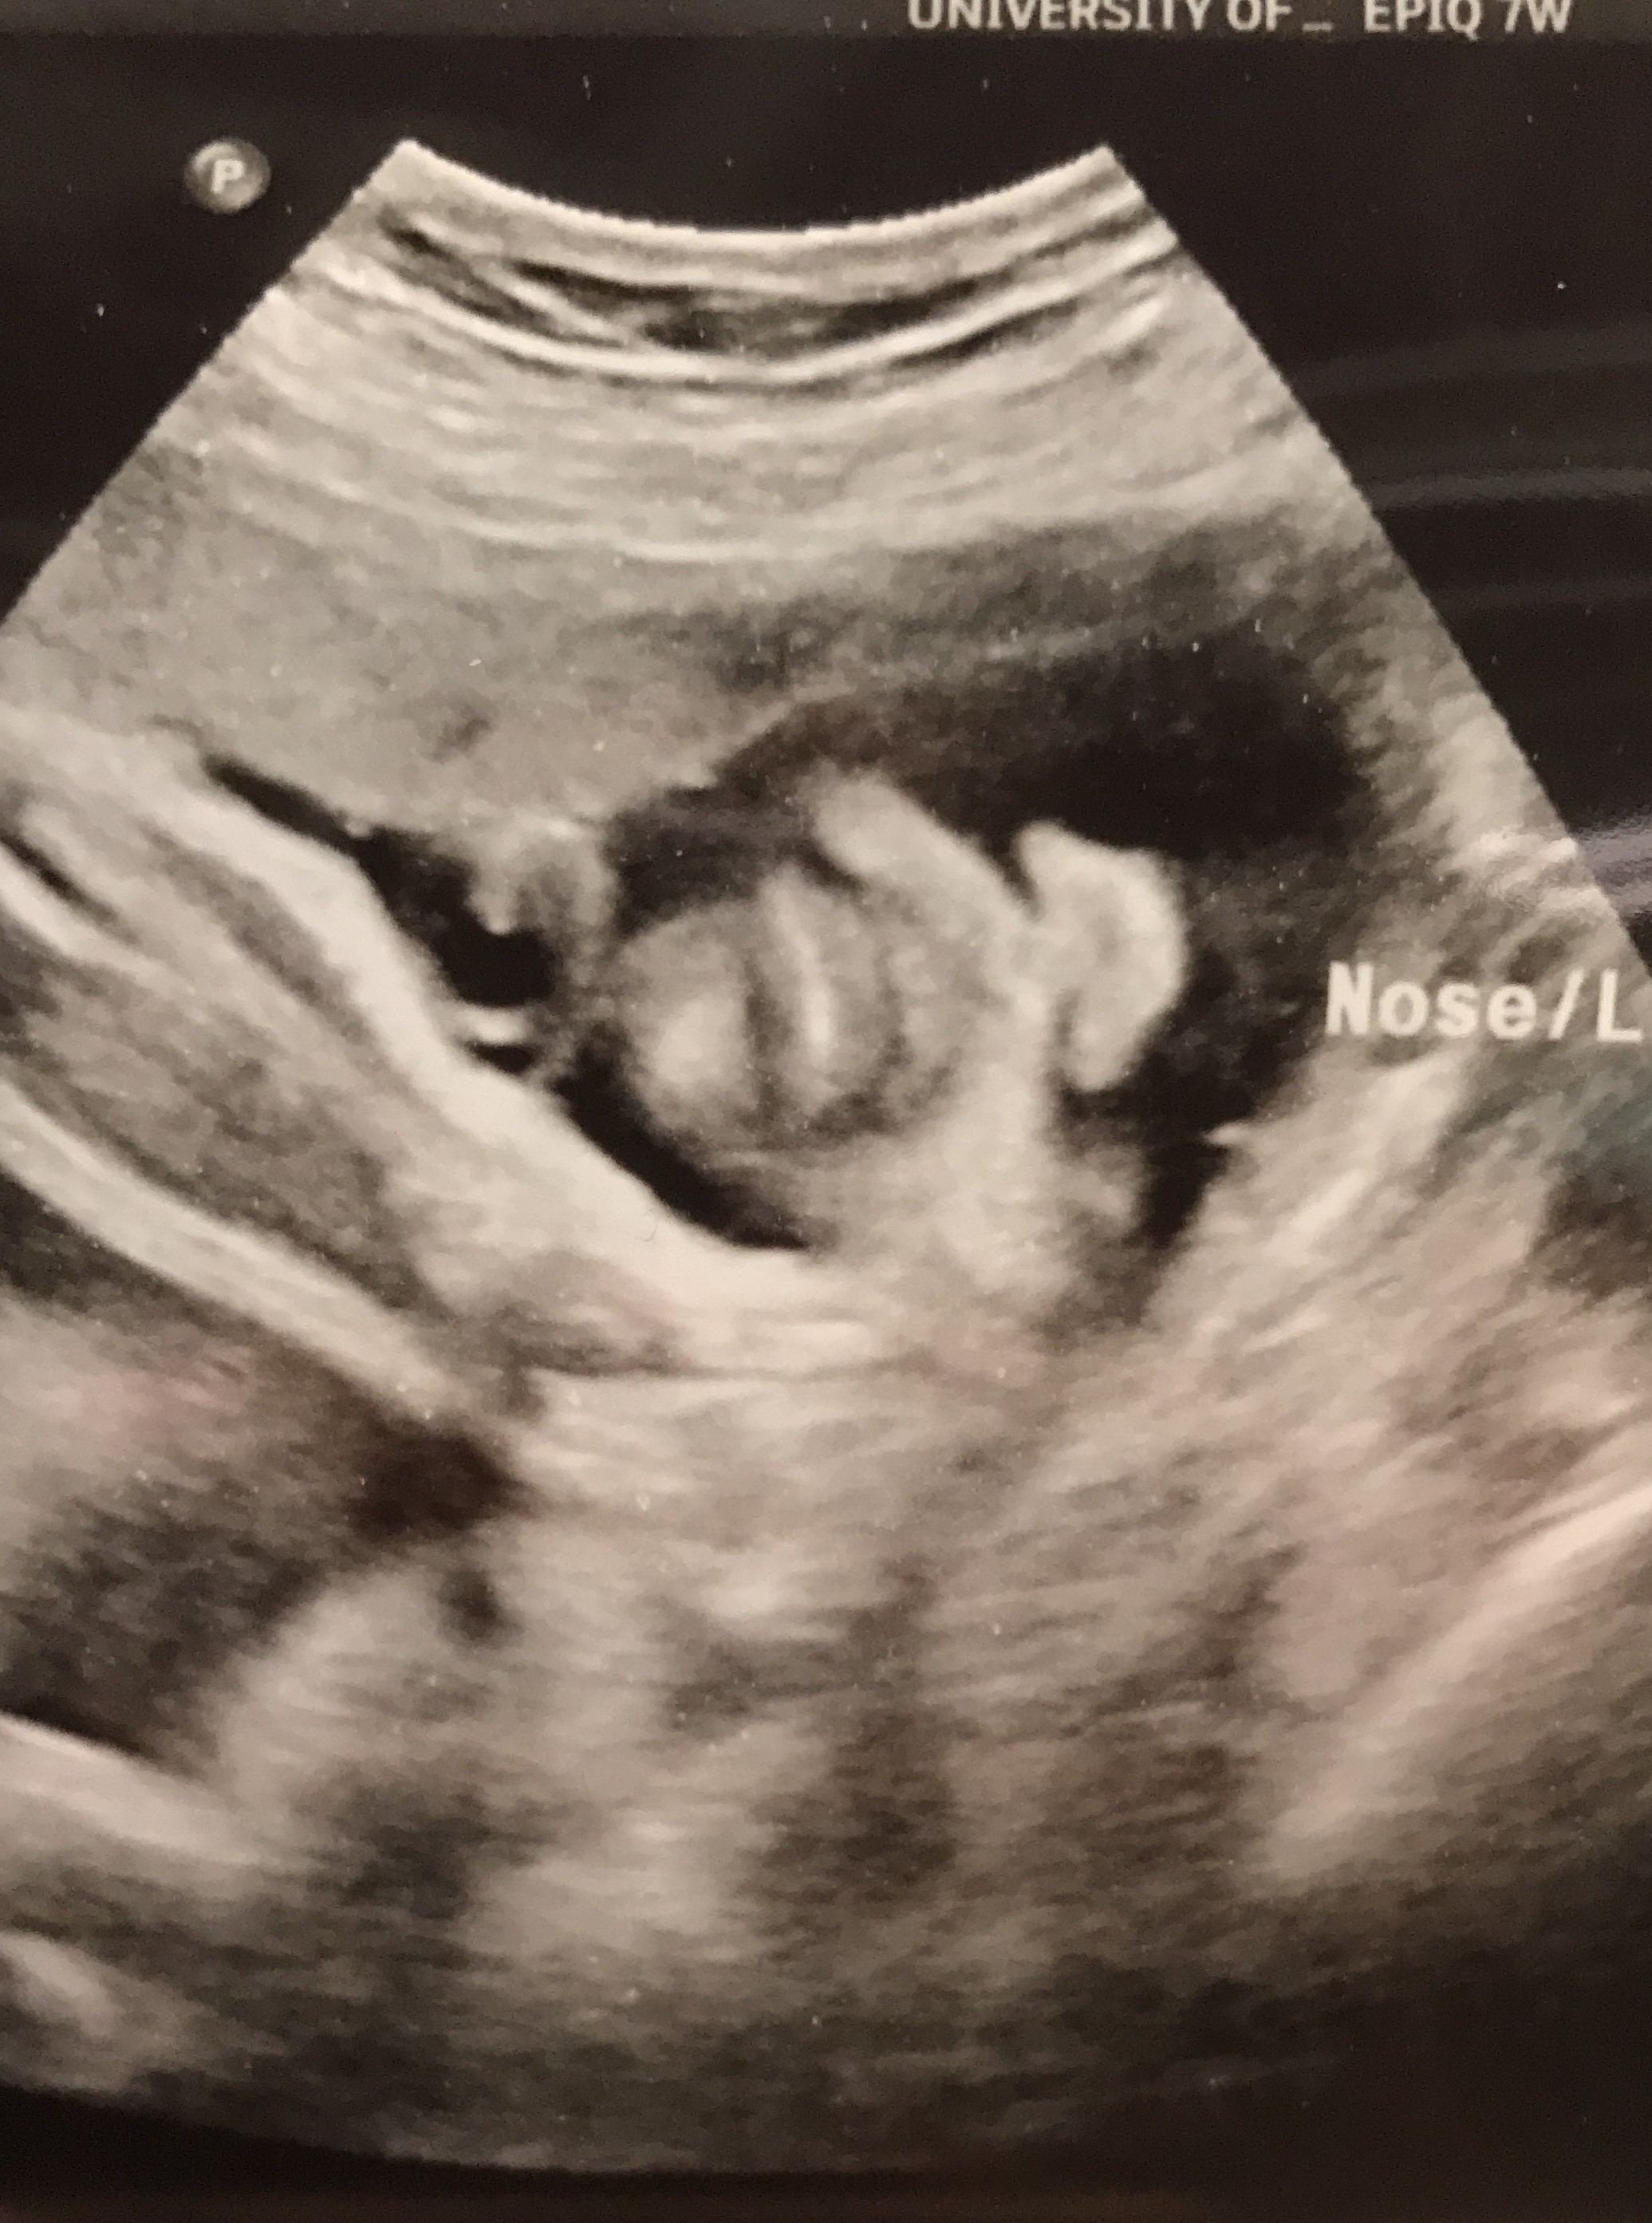

Durante la visita del doctor hicimos una sonografía para verificar el crecimiento de Francesca, ya que el doctor me dijo que estaba posicionada al igual que el doctor en Dominicana. Hasta ahora Francesca es una bebé con un tamaño normal y esperemos que siga todo normal hasta el final.